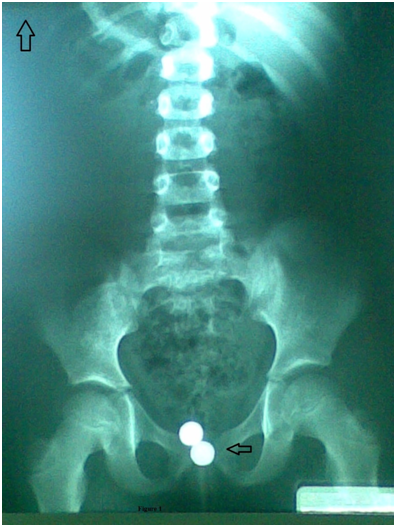

An antero–posterior radiography of the pelvis showed two radio opaque foreign bodies projecting over the pelvic inlet (Figure 1). The girl was cooperative and the foreign bodies were removed by a digital rectal maneuver that consisted of expulsing the objects from the vagina by applying anantero–posterior pressure on the vaginal posterior wall. The foreign bodies were battery watch (Figure 2).

Figure 1 Antero–posterior radiography.